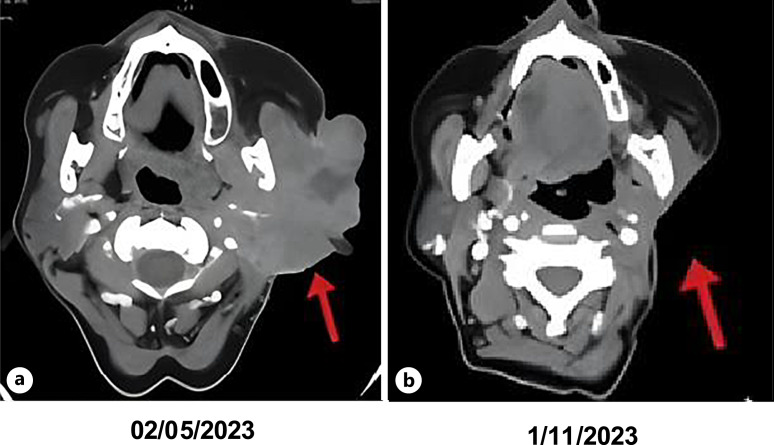

Case presentation: Here, we present the clinical journey of a patient diagnosed with unresectable salivary gland carcinoma that was refractory to both local and systemic treatments. Following molecular profiling, NTRK targeted therapy was initiated, resulting in a significant and sustained response.